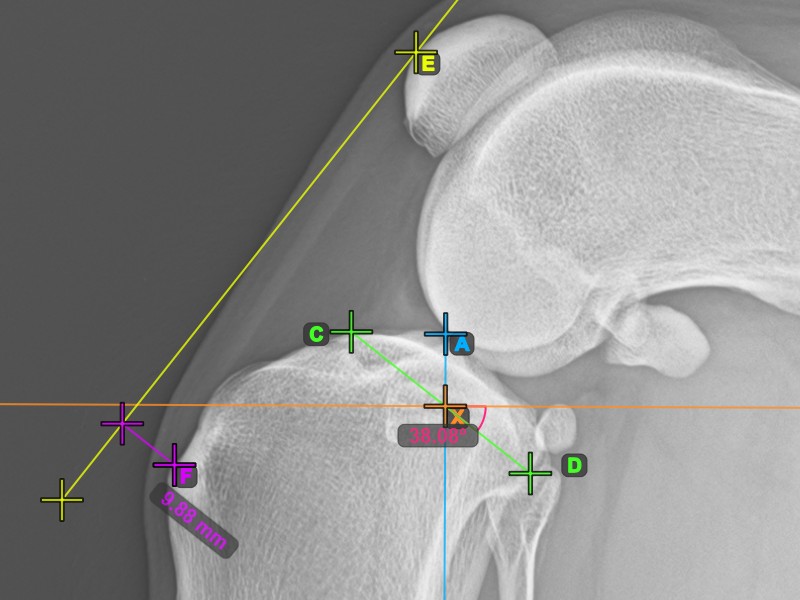

A TTA mérés eljárás befejezéséhez jelölje meg a Crista Tibiae (Tuberositas Tibiae) legdorsalisabb pontját. A Tuberositas Tibiae és a Patella legfelső pontja mentén húzott vonal közötti távolság adja meg a szükséges beállítást a TTA eljáráshoz.

A lenti kép a tibia tuberositásának, a tibia taraj legkiemelkedőbb pontjának szokásos elhelyezkedését ábrázolja.